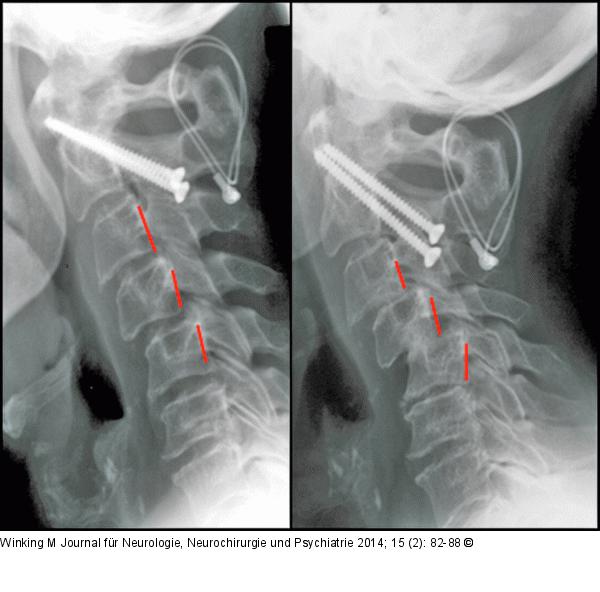

Abbildung 3: Rheumatische Wirbelsäule Seitliche Röntgenverlaufskontrolle einer subaxialen Subluxation nach 2-jährigem Verlauf. Zunehmendes Treppenstufenphänomen der Segmente HW 3/4 und 4/5. Zustand nach transartikulärer Verschraubung von HWK 1/2 4 Jahre zuvor. |